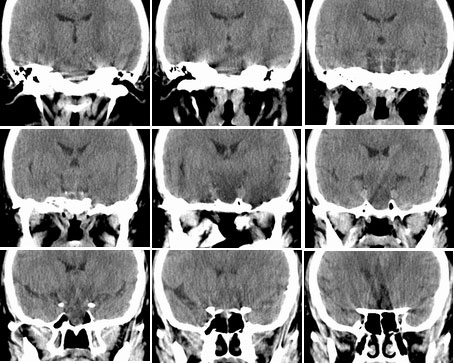

性别  女    年龄 45

阵发性头痛伴视物不清两年余

鞍区垂体窝内见一巨大类椭圆性软组织块影,前后床突受压移位、变薄,鞍底凹陷,应当能明确诊断垂体瘤。不过最好能做个mri看看视神经受累情况

蝶鞍内圆形密度不均匀,包膜完整肿块影,前床突与鞍底变薄.

意见:垂体大腺瘤.

本病例单凭ct检查是很难定位准确的,是鞍上病变侵犯鞍内、还是鞍内病变向鞍上生长?

1、如果鞍内肿瘤突破鞍隔,向鞍上生长,考虑垂体腺瘤,其典型表现是肿瘤呈"8"字征。

2、如果是鞍上肿瘤侵犯鞍内,要考虑鞍区脑膜瘤、生殖细胞瘤、实性颅咽管瘤(多为囊性、少数也可实性)、转移瘤、垂体柄胶质细胞瘤。